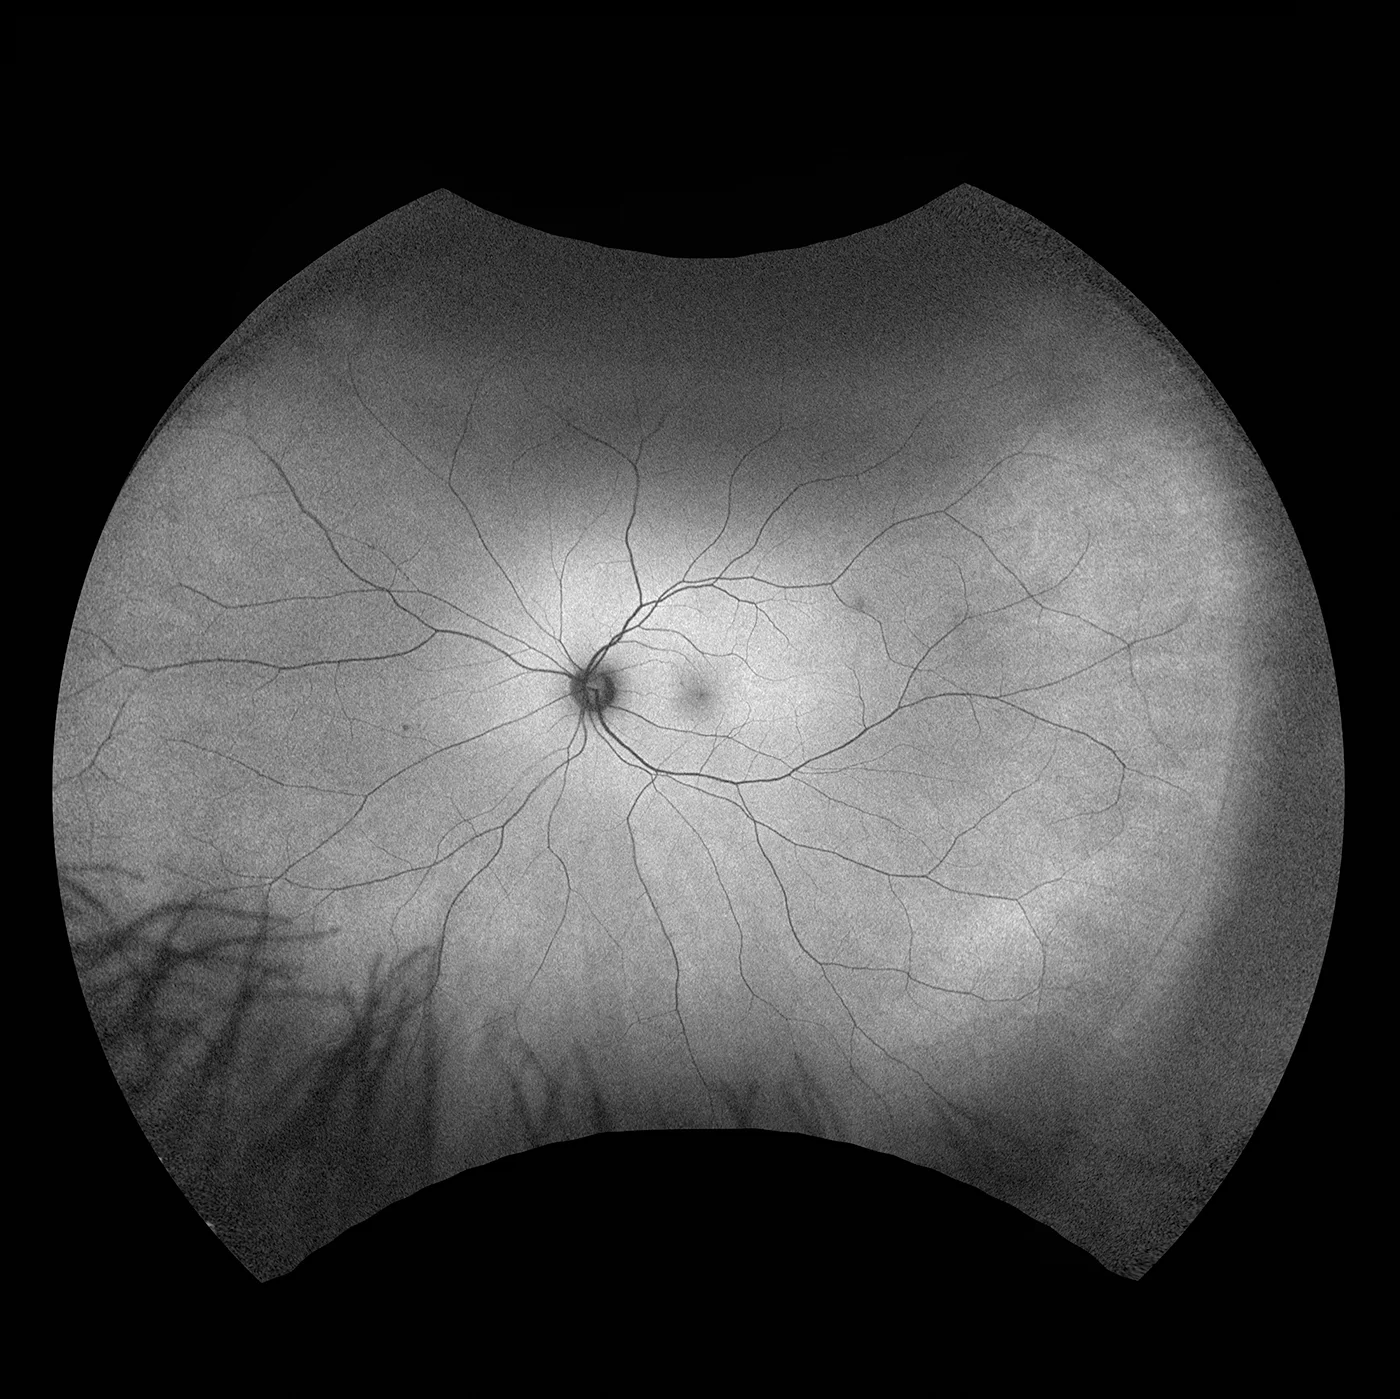

Daytona

Daytona erstellt mit nur einer einzigen Aufnahme und in weniger als einer ½ Sekunde ein 200° optomap Bild der Netzhaut von unübertroffener Klarheit. Diese schnelle, einfache und patientenfreundliche Ultraweitwinkel-Bildgebungstechnologie wurde für das Screening gesunder Augen entwickelt und verbessert nachweislich den Praxisablauf und die Patientenbindung.

Daytona-Bildmodalitäten und Darstellungsoptionen:

optomap Bildmodi

- Farbe rg

- Sensorisch Rotfrei

- Choroidal

- Autofluoreszenz